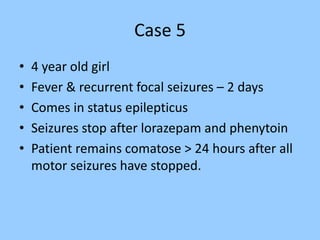

2. Case studies are presented with clinical histories and EEG findings to illustrate different pathologies. Treatment options are also mentioned for many of the conditions.